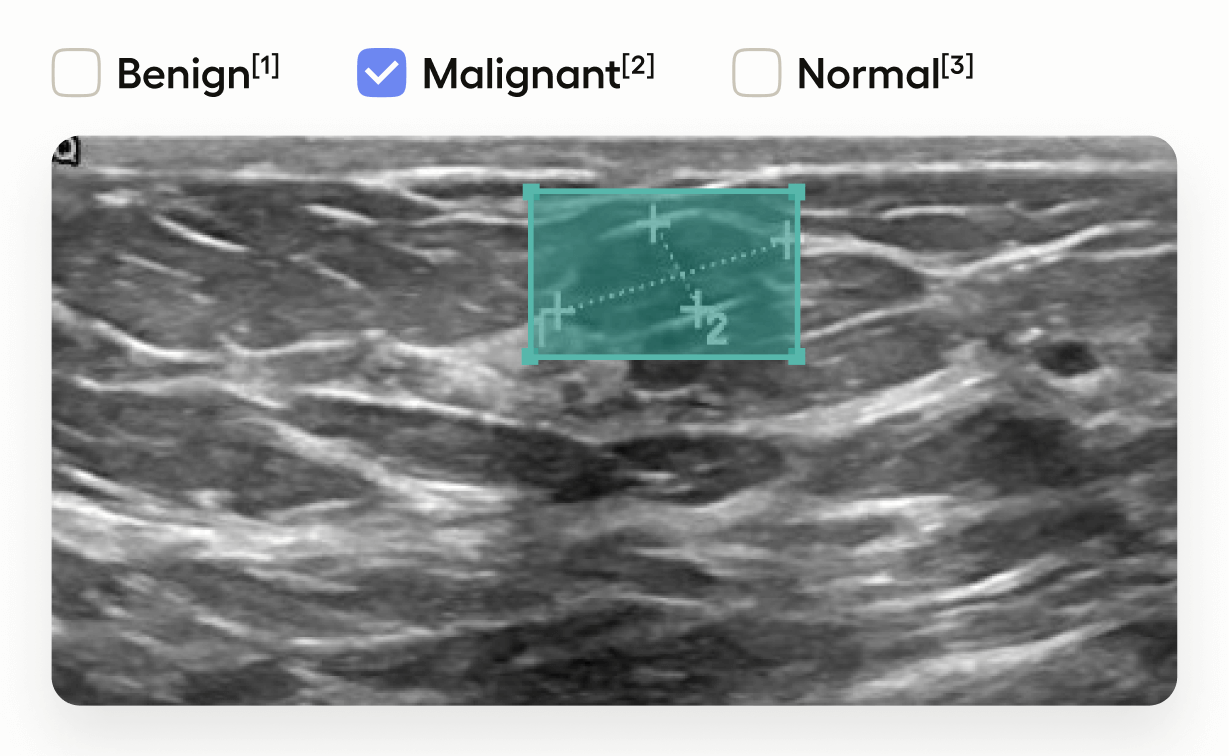

This template interface allows annotators to:

- Draw bounding boxes around areas identified as tumors in the image using the “Tumor” label.

- Classify the entire image by selecting one of “Benign”, “Malignant”, or “Normal”.

This setup is useful in medical imaging tasks where you need to localize tumors and also provide an overall assessment of the image.

This adds image-level classification choices.

<Choices>tag provides a set of options for annotators to select. toName="image"applies these choices to the entire image.- Annotators can classify the image as “Benign”, “Malignant”, or “Normal”.